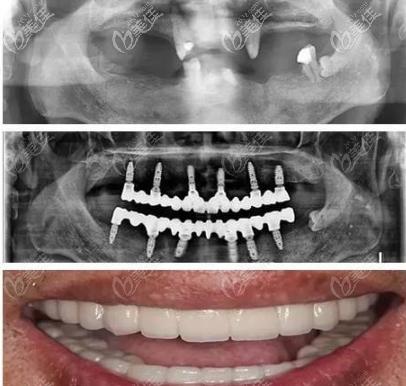

种植体与骨结合的状态可通过术后X光片观察,图片中种植体与周围骨组织紧密贴合,无透射影,表明初期稳定性良好,而长期随访图片则展示修复体使用数年后的效果,牙冠无崩瓷、牙龈无红肿萎缩,骨吸收量控制在安全范围内,印证了allon4技术的长期可靠性。

术后即刻负重的图片是最具说服力的部分,传统种植需等待3-6个月骨结合后才能戴牙,而allon4图片中,患者常在手术当天就戴上了临时牙冠,能正常微笑、进食软食,修复体的形态图片显示,牙冠的弧度、颜色、透明度与邻牙高度匹配,尤其是前牙区,牙龈乳头形态自然,看不到明显的金属边缘,模拟出天然牙的层次感,对于全口缺牙患者,术后对比图片中面部支撑恢复,避免传统活动假牙导致的“衰老面容”,咀嚼功能的恢复更是体现在患者啃苹果、吃坚果等生活场景的实拍图中。

适用人群的图片特征也较为鲜明,针对牙槽骨严重萎缩的患者,术前CT片显示骨高度不足5mm,传统种植需植骨,而allon4图片中通过倾斜种植直接利用现有骨量,避免复杂的植骨手术;对于长期戴活动假牙导致牙龈压迫溃疡的患者,术后图片显示牙龈健康无刺激,修复体与牙龈贴合紧密,无食物嵌塞问题。